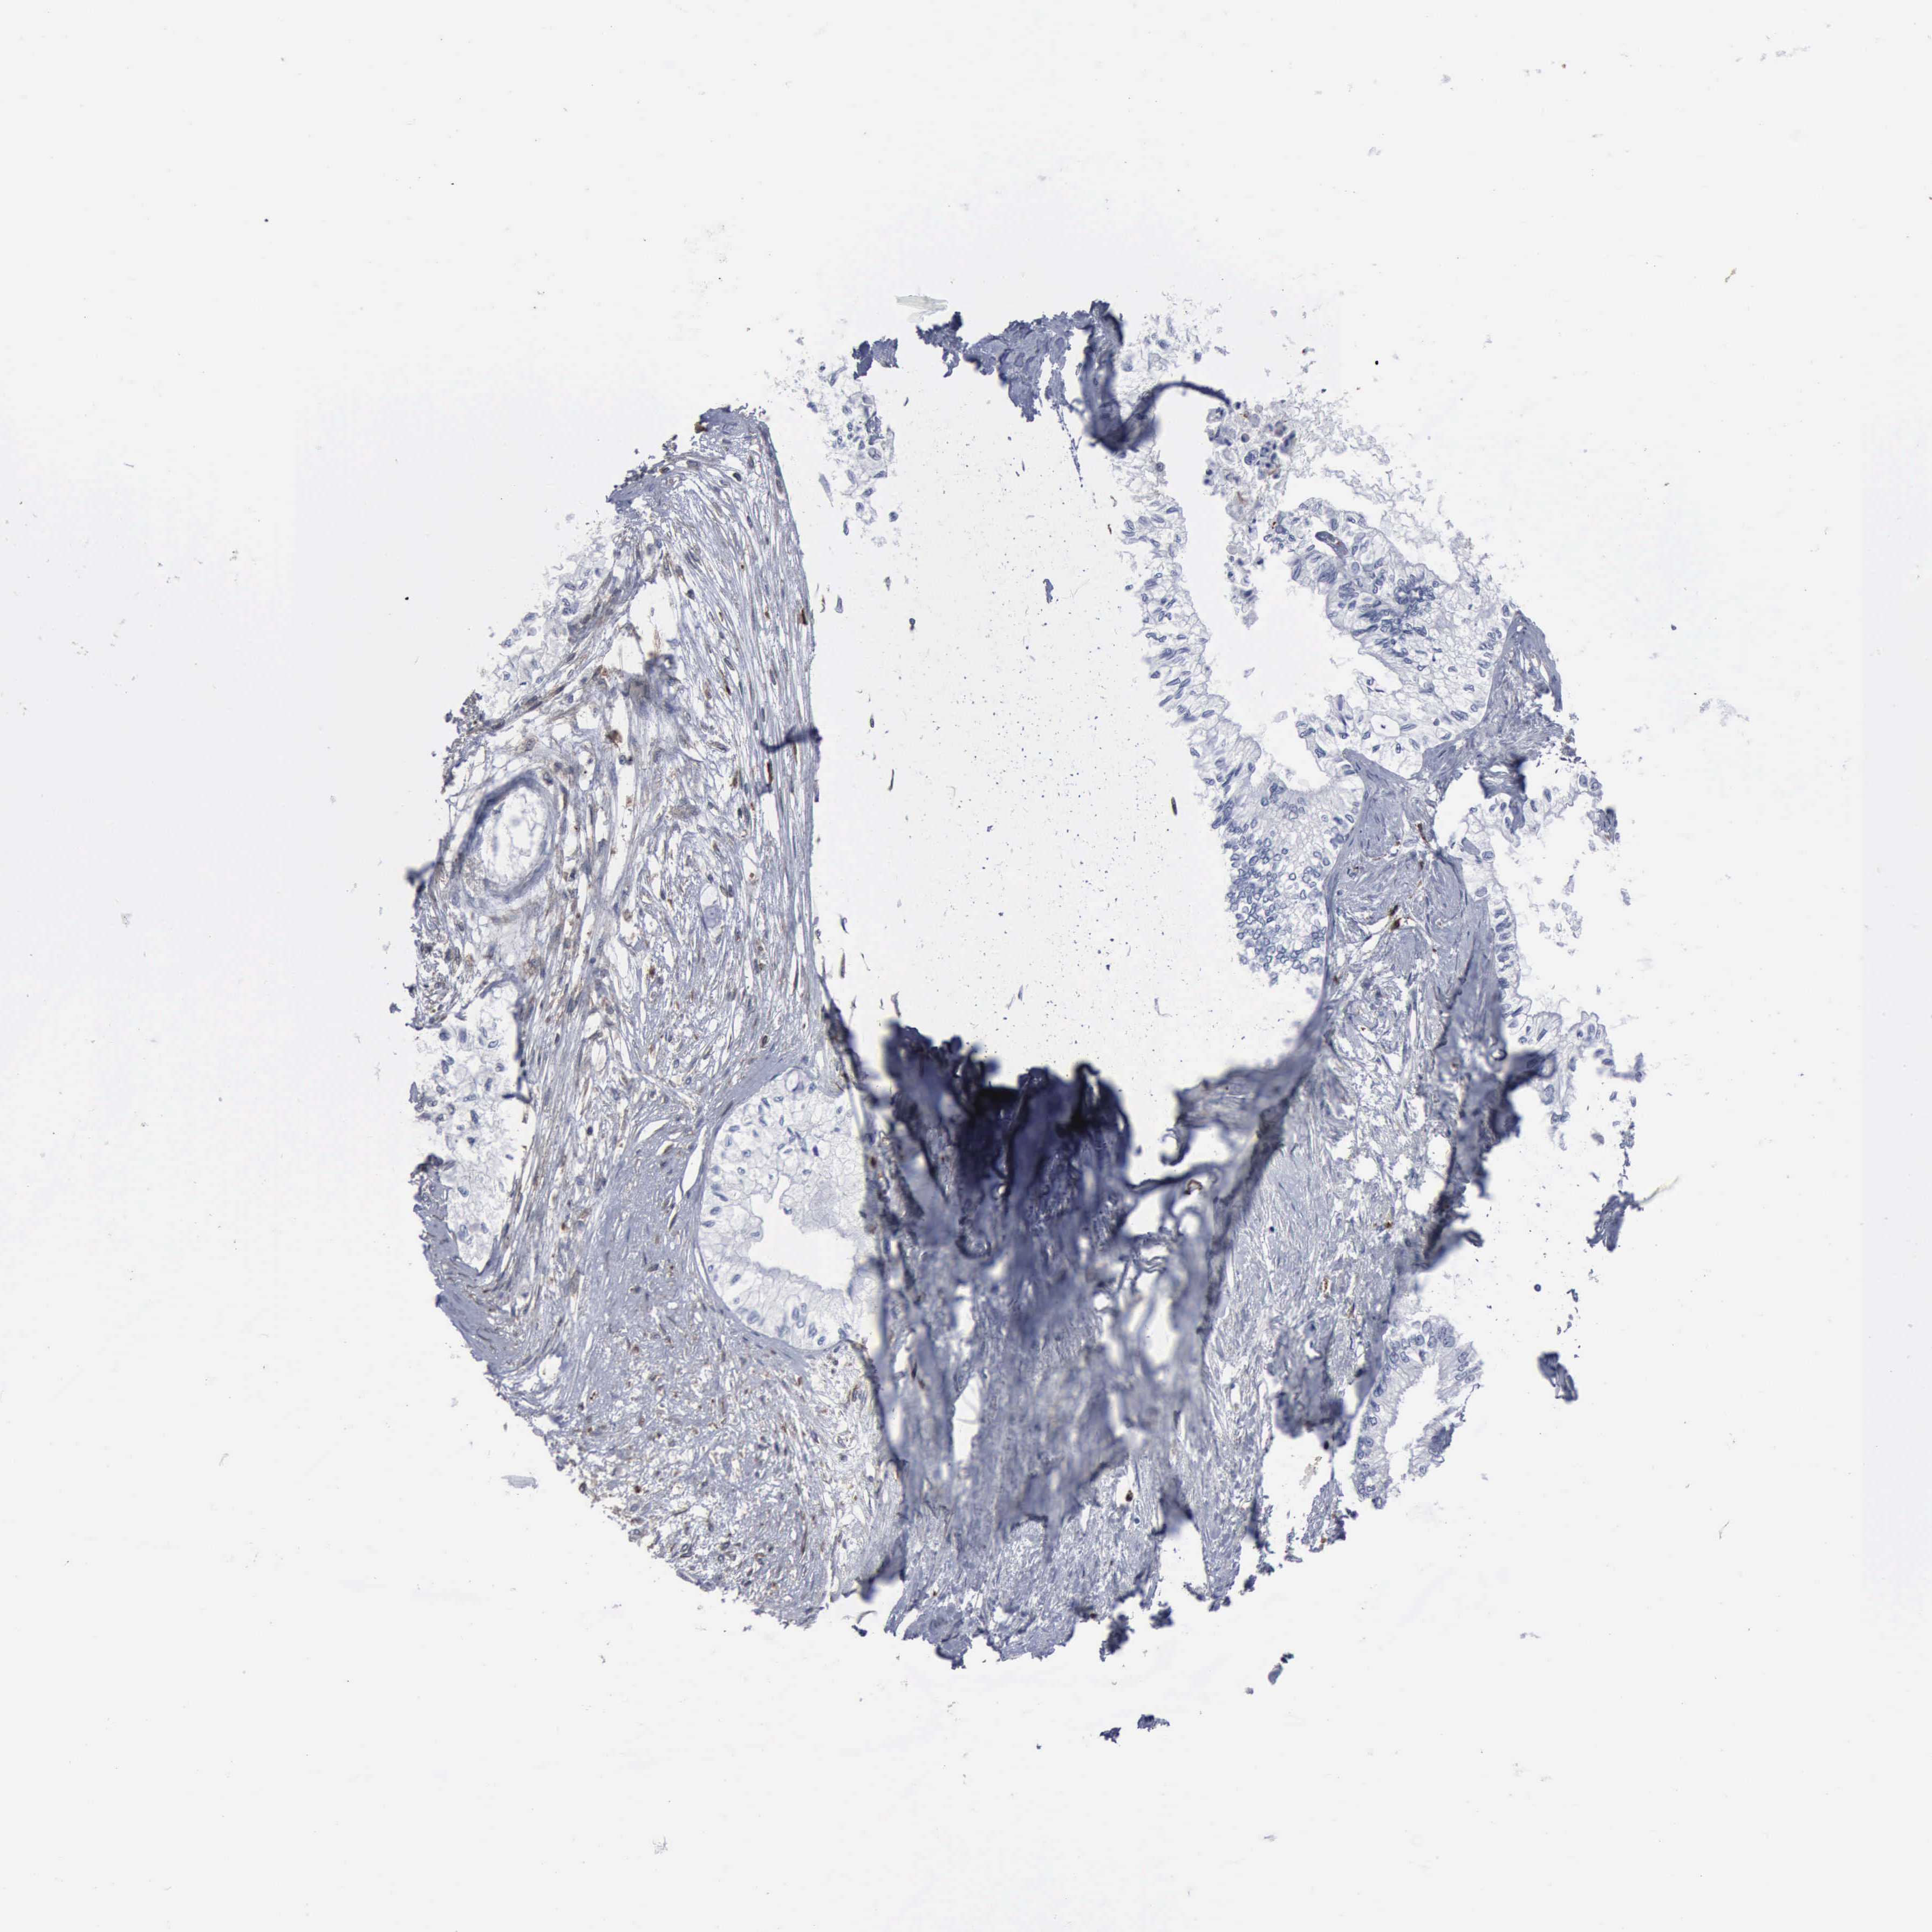

PANCREATIC CANCER - Protein expressioni

A mouse-over function shows sample information and annotation data. Click on an image to view it in a full screen mode. Samples can be filtered based on level of antibody staining by selecting one or several of the following categories: high, medium, low and not detected. The assay and annotation is described here.

Note that samples used for immunohistochemistry by the Human Protein Atlas do not correspond to samples in the TCGA dataset.

Antibody stainingi

Antibody staining in the annotated cell types in the current human tissue is reported as not detected, low, medium, or high, based on conventional immunohistochemistry profiling in selected tissues. This score is based on the combination of the staining intensity and fraction of stained cells.

Each image is clickable and will lead to virtual microscopy that enables deeper exploration of all samples and also displays staining intensity scores, fraction scores and subcellular localization as well as patient and tissue information for each sample.

Antibody HPA000962

Antibody HPA004119

Staining

High

Medium

Low

Not detected

Intensity

Strong

Moderate

Weak

Negative

Quantity

>75%

75%-25%

<25%

None

Location

Nuclear

Cytoplasmic/membranous

Cytoplasmic/membranous,nuclear

Adenocarcinoma, NOS

Adenocarcinoma, metastatic, NOS